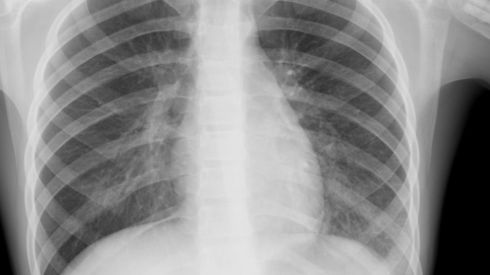

Хрипы во время пневмонии можно часто прослушать стетоскопом, но иногда этого сделать не удается. Диагноз «пневмония» ставится на основании рентгена, КТ легких, пульсоксиметрии, анализа крови и мокроты.